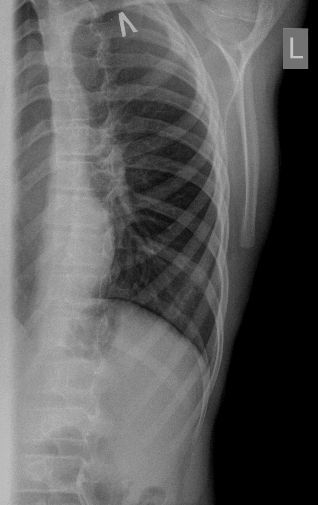

12-years old boy with torax palpable mass 5x3 cm.

Сегодня смотрел мальчика 12 лет, у которого на грудной клетке пальпируется опухоль около 5 см х3 см.

На УЗИ - такая картинка:

Деструкция корткального слоя 7-го ребра с ткаенвым компонетом, исходящим из кости. 7th rib destruction with solid mass

После УЗИ - сделал рентген, изменения в ребре есть, но в глаза не бросаются

Diagnosis of Ewing's Sarcoma is suspected